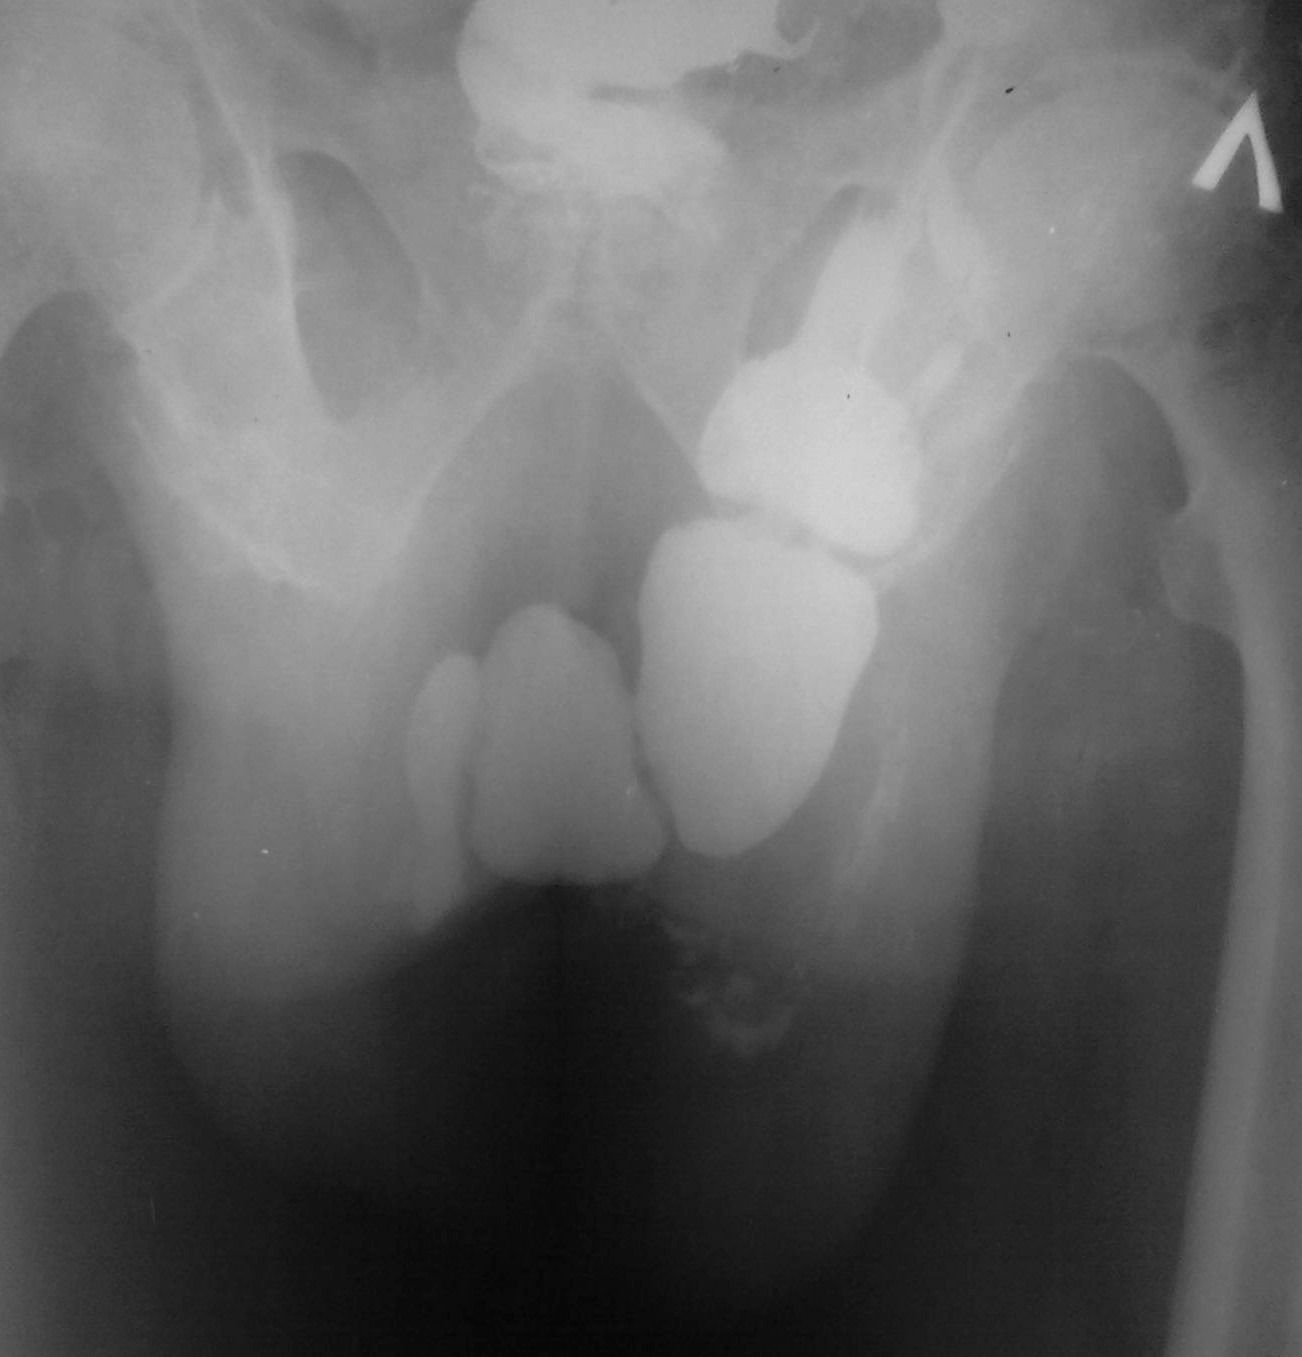

Она не в бедре, там огромный грыжевой мешок с кишками, к сожалению сохранился только этот обзорный снимок. На первое мая решил разобраться в архивах на компьютере...

Там это между ног... Это правая паховая грыжа.

Евгений Второй прав - "Не верю! Почему подвздошная кишка уходит на левое колено?"

Могу предположить наличие огромной грыжи белой линии живота, в которую вывалился "ливер" и она болтается спереди в виде "фартука".

Никак не могу представить процесс проникновения такого топически "непотревоженного" содержимого через паховый канал. В самом крайнем случае - эвентерация на уже оперированном животе. Причем у умственно отсталого, тяжело соматически больного алкоголика из глубокой тундры, так как разом такое не вываливается. В общем - "терзают смутные сомнения"...

Не верю! Автор сами знаете кто... Почему подвздошная кишка уходит на левое колено?

На момент исследования болен около 4 лет, операции боялся по этому "носил" до последнего.

По ссылке тоже просмотрел картинки. Похожа там 04 и 16. Но не так, не так.

Вот прекрасный случай Игоря Ивановича!

Досмотр кишечника через 24 часа после приема пер ос "бария".

Классическая пахово-мошоночная грыжа.